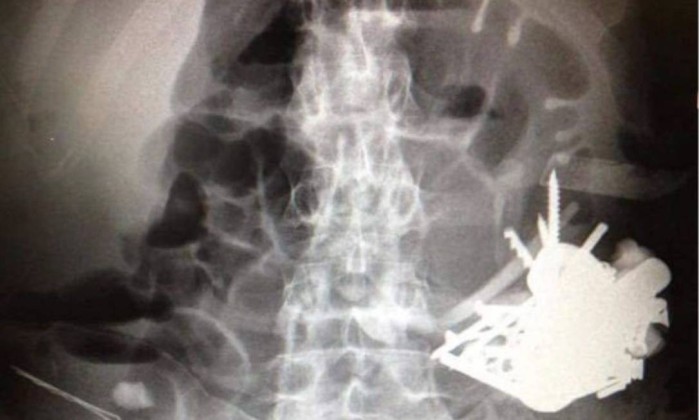

Segundo o site O Globo, o paciente procurou a emergência com febre, náusea e fortes dores abdominais e nos exames indicaram taquicardia e desidratação, mas foi em um raio-X que revelou que tinha mais de cem peças de metal acumuladas no estômago.

O site afirma que ele era portador de psicose, que tem tendência de engolir intencionalmente objetos de metal. Os exames revelaram a presença de pequenas moedas a pregos, parafusos, lâminas de faca e gilete.

Os objetos cortantes haviam feito uma perfuração no estômago do paciente.